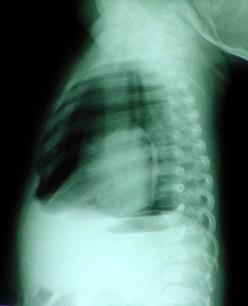

问题 患者,男性,3岁,因车祸伤半小时,急诊来院。患者呼吸极度困难,口唇发绀,烦躁不安。右侧胸部饱满肋间隙增宽,颈部胸部广泛皮下气肿。听诊右侧呼吸者消失,胸片检查如图。最可能的诊断 ( )

选项 A、创伤性窒息 B、肺爆震伤 C、血胸 D、张力性气胸 E、单纯性气胸

答案 D